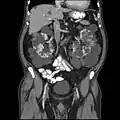

- Provádí vyšetření výpočetní tomografií – CT

CT snímek -